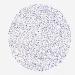

BRCA TCGA BRCA VALIDATION PROTEIN EXPRESSION

ANTIBODIES

AND

VALIDATION